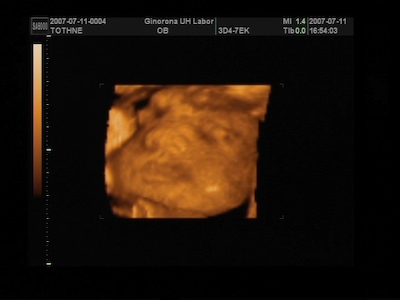

A 4D-s vizsgálaton nekem azt mondták ,hogy 5 nappal kisebb a baba, de ez még belefér ezért nem változtattak semmin , és lehet,hogy még előbb is kibújhat.